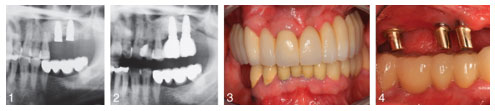

The study looks at 14 patients who underwent two procedures involving tooth replacement. In the first procedure, patients received a bone substitute, composed from nanocrystalline hydroxyapatite, which was grafted into the patient’s jaw. This synthetic material provided scaffolding for new bone growth, expanding into patients’ upper jawbone. Half of the patients then waited three months while the other half waited six months before undergoing the second procedure, placement of the dental implant(s).

The study found similar results among patients three years after the dental implants, whether patients waited three or six months between procedures. The 14 patients collectively received 24 implants in the upper jaw, and only 1 patient lost an implant. No implants were loose, and only a few showed signs of plaque or changes to soft tissue.

Full text of the article “Nanocrystalline hydroxyapatite-based material contributes to implant stability after three months: A clinical and radiological 3-year follow-up investigation,” Journal of Oral Implantology, Vol. 40, No. 1, 2014, is now available online.